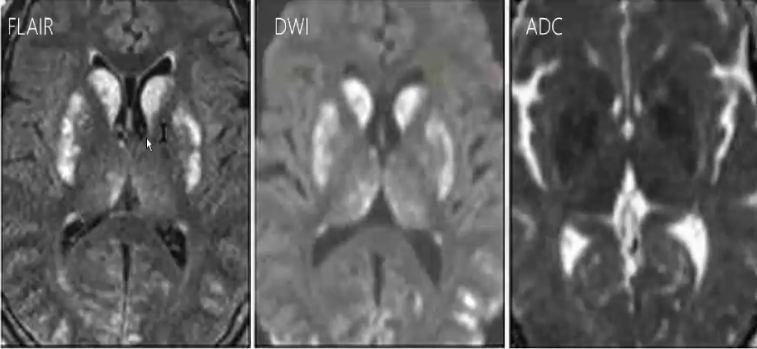

缺血缺氧性脑病

❖ 当血流减少超过前循环到后循环的反射性分流代偿机制的上限,会导致大脑深部核团、脑干、大脑皮层的损害。DWI是能够在最早期发现异常的影像改变。

男,64岁。患者具有长期缺氧史